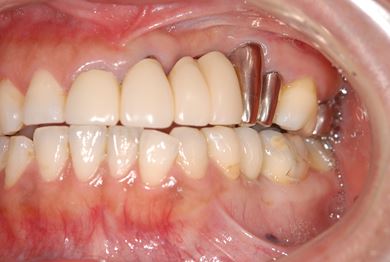

| 性別/年齢 | 女性 / 45歳 | ||||||||||||||||||||||||||||||||

| 主訴 | 以前治療した歯の歯ぐきから出膿。他の歯科でインプラントかブリッジしか方法がないが、骨の状態からインプラント治療は無理かもしれないと言われたことに不安を感じ、セカンドオピニオンを求めて来院。 | ||||||||||||||||||||||||||||||||

| 治療方針 | 保存不能の歯を抜歯し、インプラント治療にて機能的・審美的回復を行う。 | ||||||||||||||||||||||||||||||||

| 治療内容 | インプラント1本、ハイブリッドセラミッククラウン1本 | ||||||||||||||||||||||||||||||||